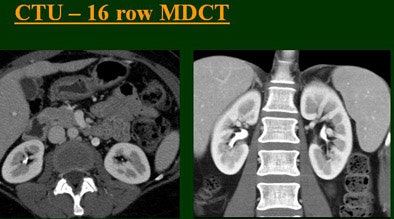

"As we've been scanning through the kidneys, we've been noticing that there has been an increase in the quality images as we go from (single-) to four-, eight-, and 16-row detector scans," Raptopoulos said. "Our purpose, then, was to assess the quality of CTU with progressively improving CT technology from (single-) to 4-, 8-, and 16-row scanners, using a split-injection single scanning technique."

| Top to bottom: Split-bolus CTU improves significantly using a nearly identical protocol but with the addition of more detector rows, from single- (spiral), four-, eight-, and 16-row scanners. All images courtesy of Dr. Vassilios Raptopoulos. |

The single-row scanner required two breath-holds; the other scanners reduced scan time from about 20 seconds (four-slice) down to seven seconds (16-slice). Collimation for the single-row scanner was 5 mm, with 3-mm overlapping reconstructions. Collimation for the four-, eight-, and 16-row scanners was 2.5 mm, 1.5 mm, and 0.5 mm, respectively, with the patients scanned in a prone position.

Based on multiplanar reformatted (MPR) images, there was significant upscale improvement in calyceal detail from the isotropic images provided by single-detector scanning (median score 2) to four- (median score 3), eight- (median score 4), and 16-detector scanning, Raptopoulos said. On MPR images the calyceal were 1, 2, 3, and 5, respectively. The median ureteral filling was 4 for the upper and left-lower ureters, and 3 for the right-lower ureters.

"We're using this technique of biphasic injections not only in CTU, but in general abdominal scanning in trauma, in renal CT, and we can see the renal vessels quite well in relation to the collecting systems," Raptopoulos said. "Combined excretory- and parenchymal-phase CTU is a practical technique, allowing a decrease in patient scanning," he said. "Sixteen-row CTU with the patient in a prone position significantly improves the quality of the exam."